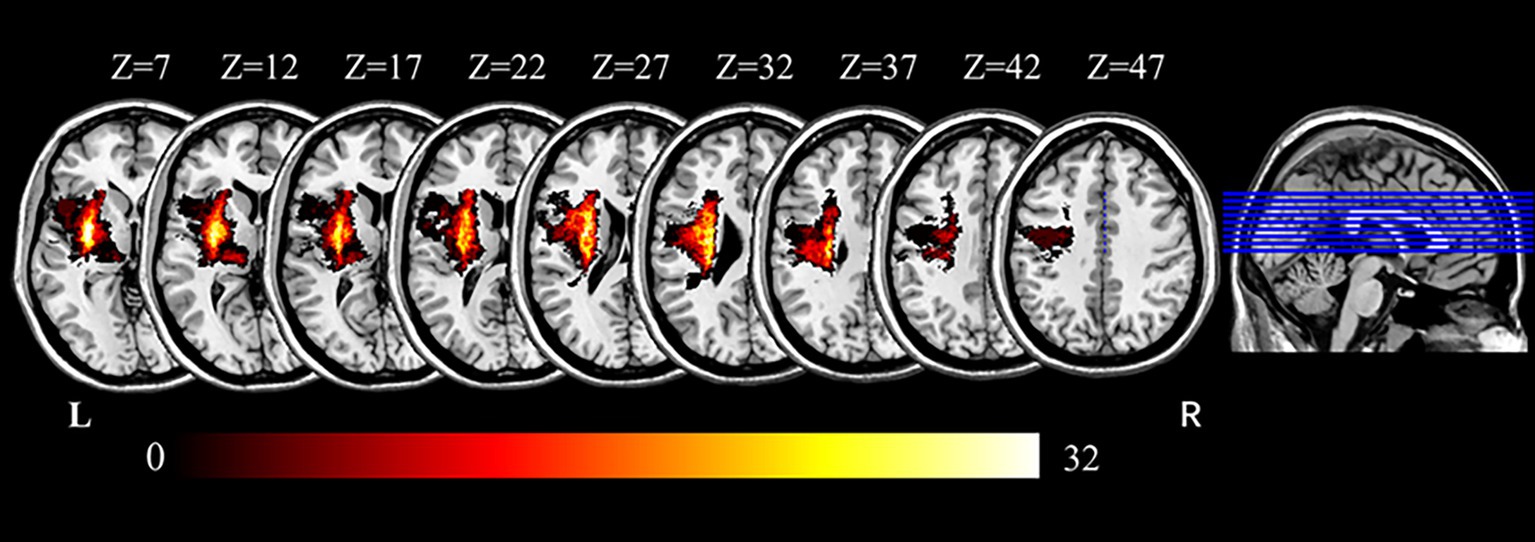

Lesion volumes were manually delineated on T1- and T2-weighted images by two experienced radiologists using MRIcron software1. Lesions were outlined slice by slice for each patient, with T1-weighted images used for primary outlining and T2-weighted images used for validation. To standardize lesion laterality, all images were mirrored so that lesions were represented on the left hemisphere (Figure 1). The resulting lesion masks were used for visualization, lesion volume calculation, and exclusion of intra-lesion voxels during dFC analysis. Notably, lesion volume was not significantly correlated with UL motor function, as measured by UL-FMA scores (Pearson’s r = −0.208, p = 0.087), suggesting that stroke size alone did not account for impairment severity in this cohort.

Figure 1

Overlap map of stroke lesions across all participants. Color intensity indicates the number of patients with overlapping lesions at each voxel. Axial slices are displayed along the z-axis from slice 7 to slice 47 in Montreal Neurological Institute (MNI) space (MNI, Montreal Neurological Institute; R, right; L, left).